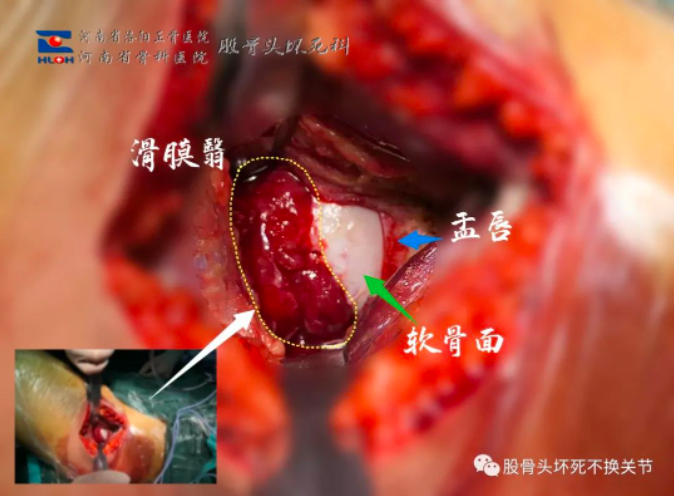

上图,黄色虚线内即为股骨头周围增生的滑膜血管翳,其对股骨头的不利作用显而易见。另外,软骨面、盂唇尚未发生明显病变。